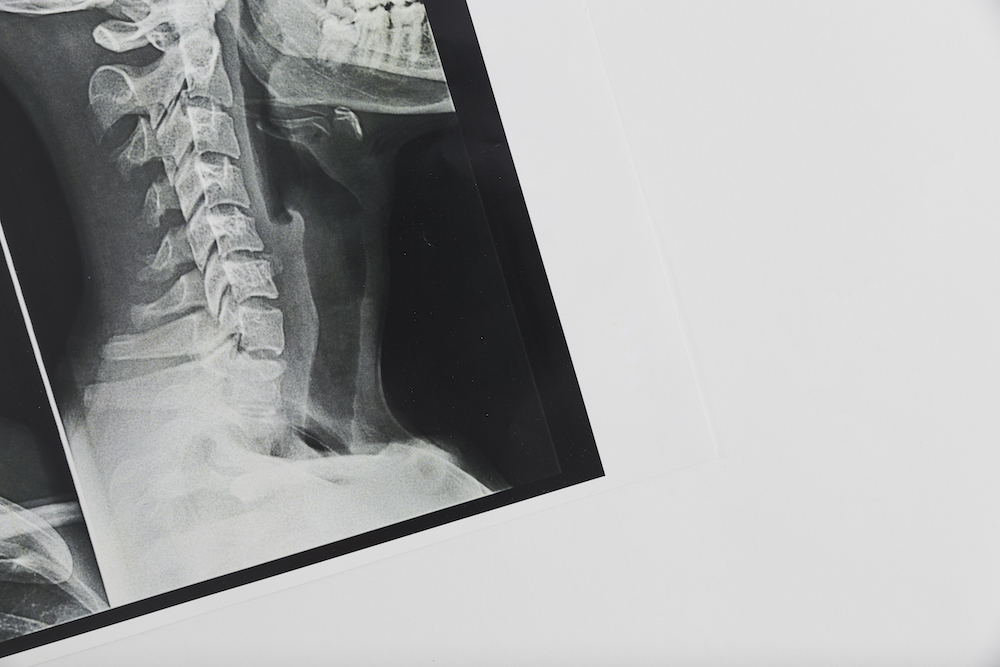

Getting an x-ray of your spine gives us an extremely detailed look at what’s going on with your spine. Many times, this can help us confirm the diagnosis and give us confidence in the right treatment plan to help getting you back to optimal health.

If you’ve been experiencing back pain, neck pain, or headaches, or other discomforts, a spinal x-ray can help us identify the cause and give us a clear path for treatment.

a chiropractor show the result of the spine X-ray result

A spinal x-ray can give our chiropractor in Conroe important information about your spine. The imaging can help diagnose problems with your bones, joints, and discs. A spinal x-ray can also help find problems with the ligaments, muscles, and other soft tissues in your back that are tougher to diagnose without the images.

Usually taking x-rays only take a few minutes. Once we are done grabbing the images, we will be able to review them on our computers within minutes. We can show you the images and talk through exactly what we are seeing and how this is playing a role in your health.

Spine X-rays can reveal herniated discs, scoliosis, degenerative disc disease, arthritis, spinal misalignments, fractures, and other structural problems. At Rodgers Stein Chiropractic , Dr. Stacey Rodgers uses X-rays to guide personalized chiropractic care for patients in Conroe.